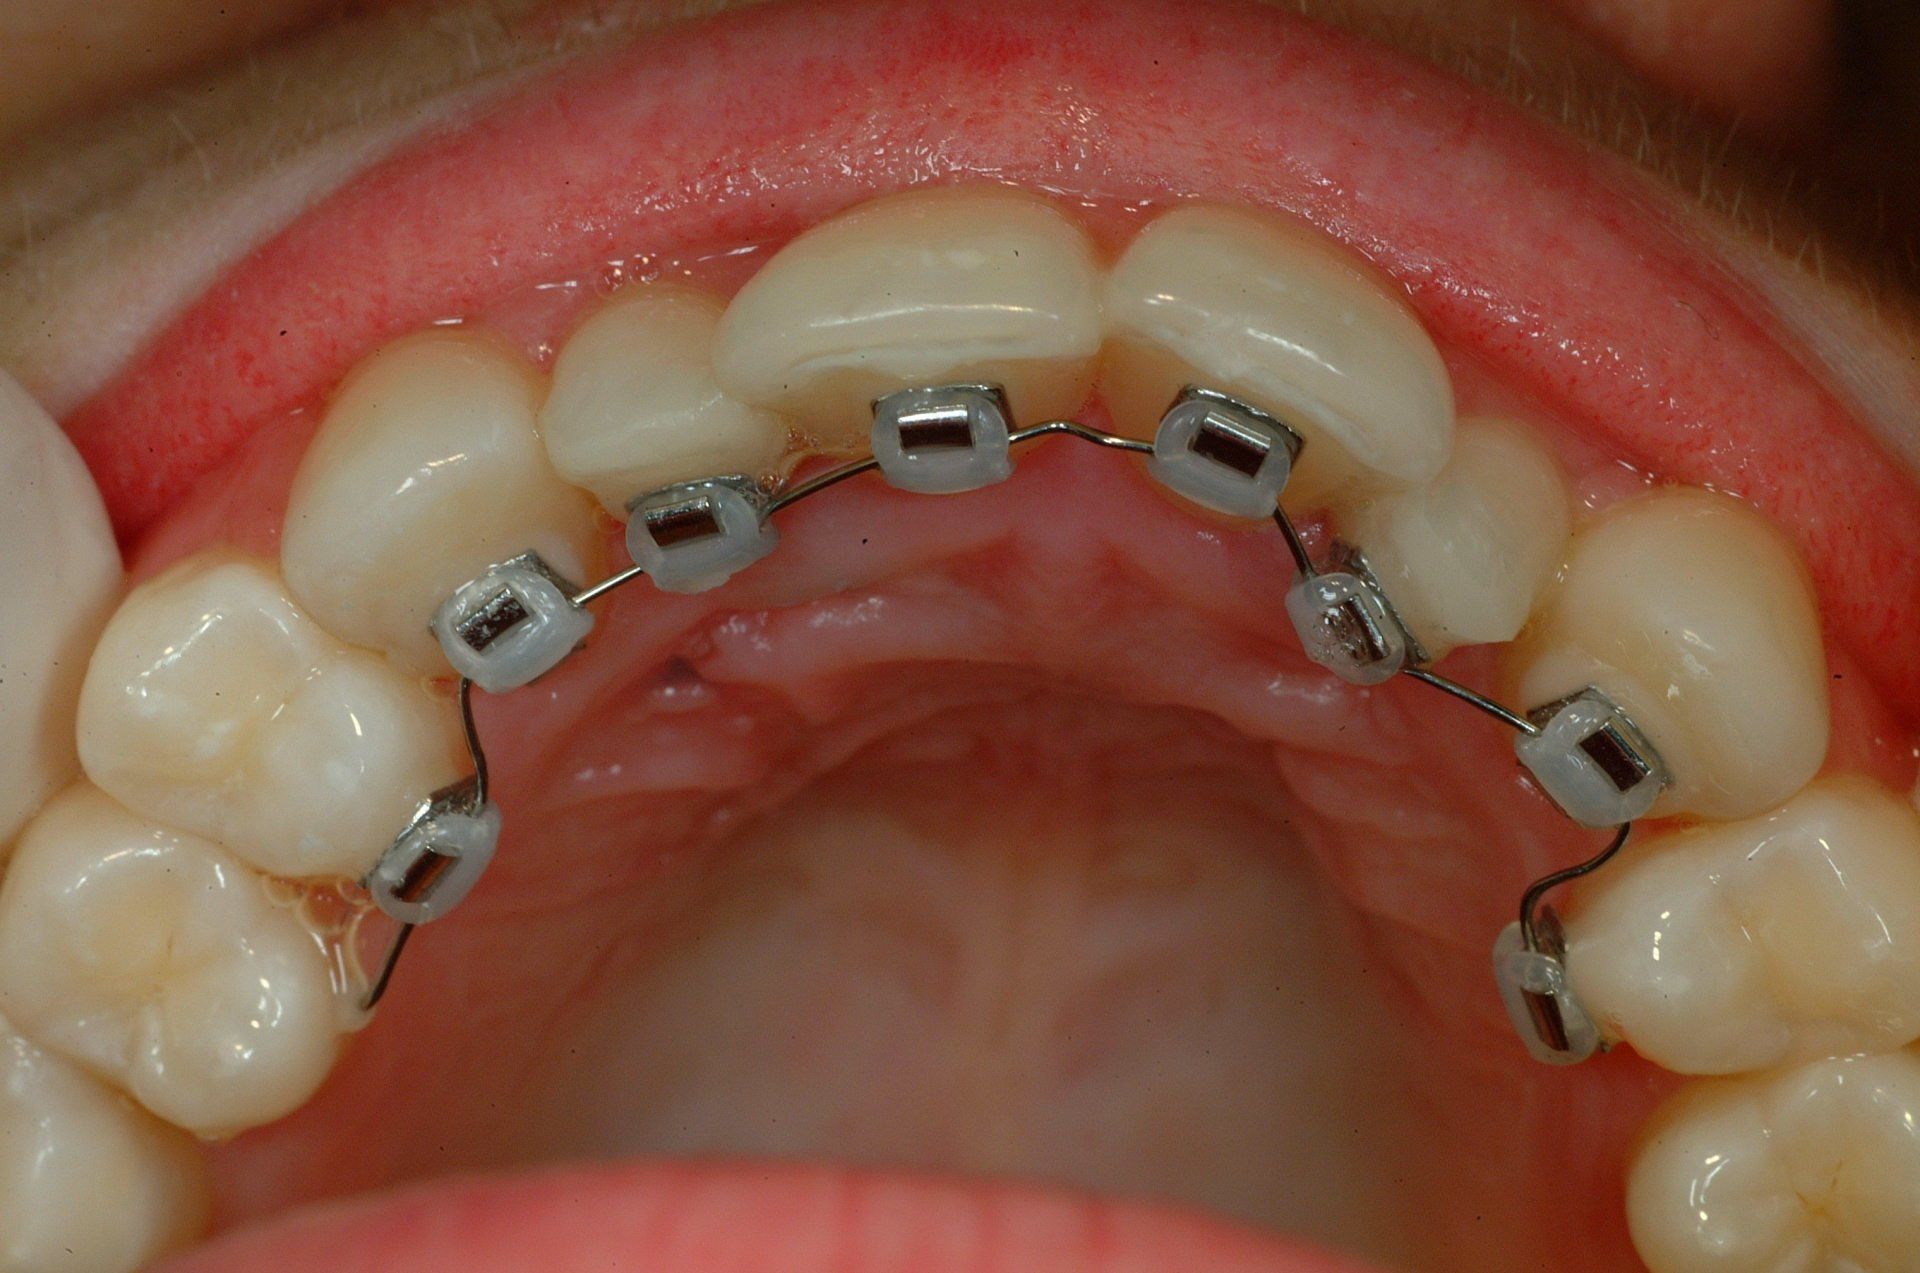

Alcuni casi dello Studio